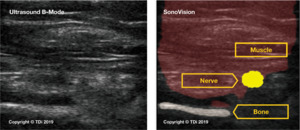

2.2 Introduction to Device

SonoVision™ provides an answer to many of the unmet needs in terms of intraoperative imaging for spine surgery. The use of a machine learning algorithm and numerous rounds of data training allows SonoVision™ to differentiate between various soft-tissue types and structures (bone, nerve, and vascular structures). It uses this information to create a real-time overlay for high-quality ultrasound imaging which highlights and color codes key anatomical structures such as nerves, muscle, bone and blood vessels (Figure 4). While other devices may provide higher image resolution, the tradeoff of near instantaneous images, accurate identification of key soft tissue structures, and low risk and cost for the patient make this a more effective intraoperative imaging device.

In preclinical trials, SonoVision’s™ accuracy was assessed based on its ability to correctly and judiciously identify and differentiate tissue types including muscle, bone, nerves, and vasculature. In preclinical animal studies, SonoVision™ demonstrated 100% accuracy for tissue differentiation and identification (Figure 9).

A simulated usability study applied the trained SonoVision™ ultrasound system with Beluga1TM probe to a surgical setting which was representative of what physicians would encounter in a real scenario. This study involved the use of 5 porcine subjects with all protocols previously approved by IACUC. The primary objective was to assess and validate the SonoVision™ system’s ability to locate nerves, vasculature, and bone and facilitate safe navigation around key soft-tissue structures to access the target disc space. Metal pins represented the “clear-path” to vertebral spaces identified using the system and the presence of nerves or vasculature were subsequently evaluated within the vicinity of each pin. Of the 24 pins placed in the 5 animals, all SonoVision™ imaging notes matched with the corresponding dissection notes representing a 100% accuracy for all tissue type identification (Figure 10).

In addition to imaging of potential nerve locations, the ability of the SonoVision™ software to identify bone in a given image was also tested. Again, pins were inserted through the psoas muscle to the spinal column using the imaging system, and the presence of bone was initially confirmed by the surgeon through touch. All pin locations used for identification of nerve tissue and clear paths were also evaluated for presence of bone and musculature (Figure 11). The Stealth Imaging and Navigation system (Medtronic, USA) was used to confirm the presence of bony surfaces, as well as the depth of both bone and muscle as measured by the SonoVision™ system. Dissection was again used to confirm the presence of target structures. All structures identified and measurements reported by SonoVision™ corresponded with assessments by both surgeon and the Stealth imaging system. This represented accuracy of 100% for identification of bone as well as measurement of tissue depth. Lastly, blood flow imaging was obtained using SonoVision™ ultrasound’s color flow doppler. Blood flow imaging was completed for a total of 24 cases from 3 animals and validated through dissection (Figure 12) and reported accuracy of 100%.